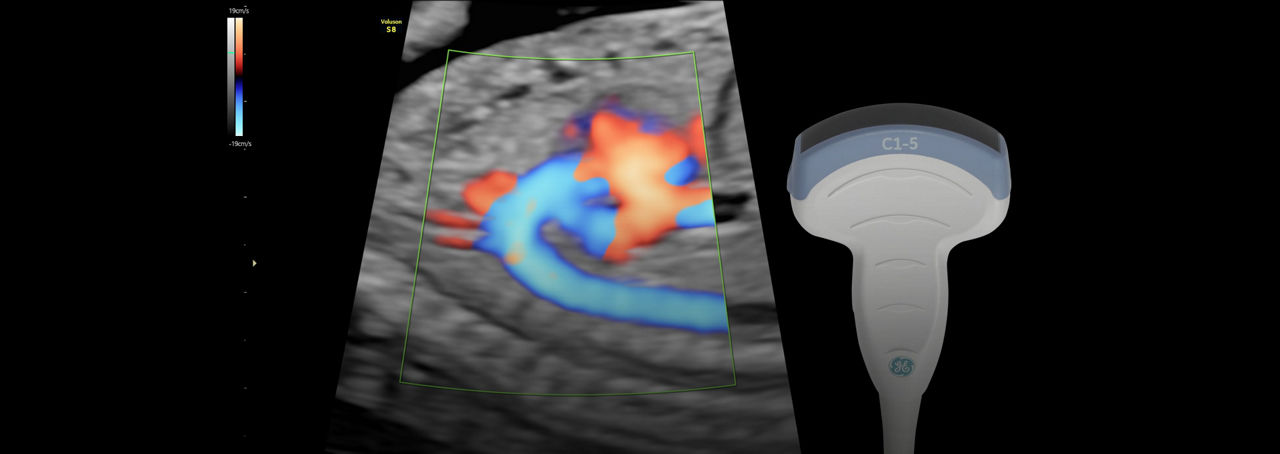

Exceptional Color Sensitivity

Enhance visualization of small vessels and borders of the fetal heart with Radiantflow™; powering greater color sensitivity for a more dynamic 3D-like appearance.